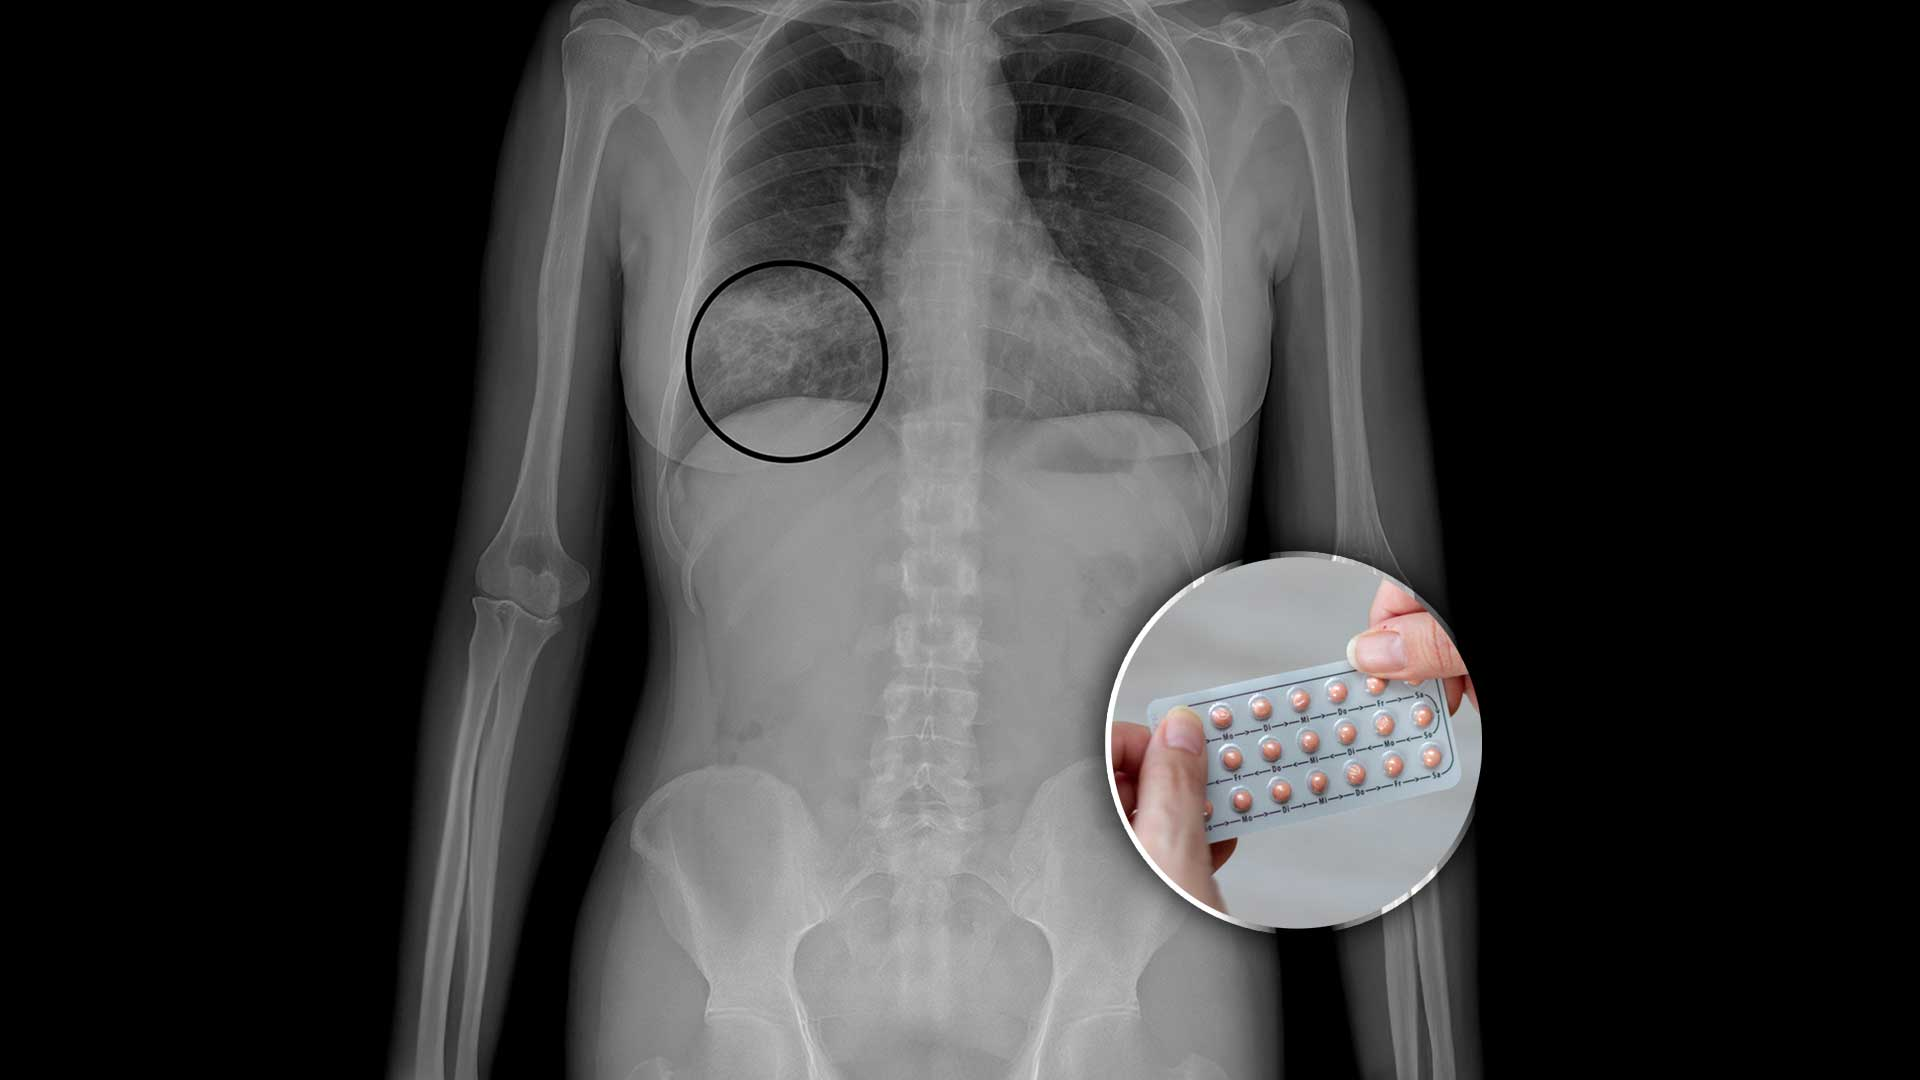

1. Sí aumenta el riesgo de algunos cánceres… pero protege contra otros

La OMS clasifica a los anticonceptivos hormonales combinados como carcinógeno tipo 1.

Esto no significa que causen cáncer automáticamente, sino que existe evidencia científica de que modifican ciertos riesgos.

📌 Aumenta ligeramente el riesgo de:

Cáncer de mama

Cáncer de cuello uterino

📌 Disminuye el riesgo de:

Cáncer de ovario

Cáncer de endometrio

Cáncer de colon

👉 La realidad es esta: el riesgo absoluto es bajo, pero existe, y toda mujer tiene derecho a saberlo antes de usarla.